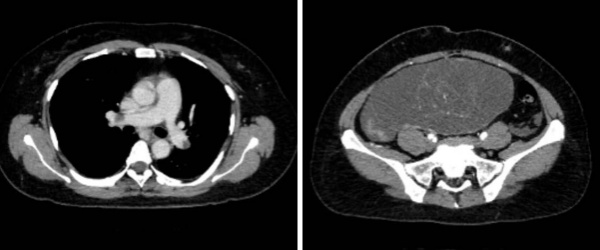

2024年2月,董女士因左小腿疼痛两周就医,CT检查如同晴天霹雳,盆腔内 18.3×17.3cm 的巨瘤几乎填满盆腹腔,肿瘤标志物CA19-9飙升至 10000U/mL 以上,更凶险的是——双下肢深静脉血栓已形成,双肺动脉主干远端、右肺中下叶及左肺下叶布满血栓,随时可能引发致死性肺栓塞!

术后 48 小时是血栓风险巅峰期:重症医学科董英俊副主任医师团队每日监测D-二聚体指标,通过振动排痰、气压治疗等措施预防血栓再生;护理团队定制体位管理法,在保证伤口愈合的同时避免静脉淤滞。术后第3天董女士自主呼吸平稳,血栓指标降至安全线,从ICU转入普通病房;第7天,她恢复良好带着新生般的笑容办理出院,CT 显示盆腔术区清洁,双肺血栓稳定无进展。